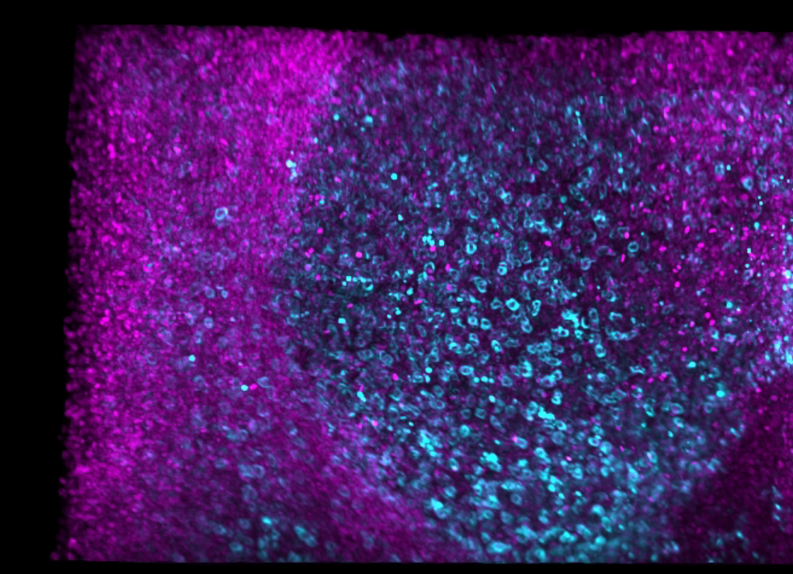

Identification of B Cells and Follicular Dendritic Cells through CD21 Staining

Low resolution image of human tonsil measuring up to 3mm in x,y,z, stained with Biocare Bu32 anti-CD21. This antibody has been optimized for a variety of human tissue including FFPE samples.

Identification of Memory T-Cells through CD45RO Staining

High resolution image of human tonsil measuring up to 3mm in x,y,z, stained with Biolegend anti-CD45RO. This antibody has been optimized for a variety of human tissue including FFPE samples.

Deep Tissue Staining with anti-CD3 to Identify T-cells

Low resolution image of human tonsil measuring up to 3mm in x,y,z, stained with Biocare Medical BC33 anti-CD3. This antibody has been optimized for a variety of human tissue including FFPE samples.

Identifying cytotoxic T-cells in cleared, thick tissue samples through CD8 Staining

Low resolution image of human tonsil measuring up to 3mm in x,y,z, stained with Biocare Medical SP6 anti-CD8. This antibody has been optimized for a variety of human tissue including FFPE samples.

3D Visualization of Cytotoxic T Cells and Macrophages Using CD8 and CD68 Staining

Explore the intricate distribution of immune cells in human tonsil tissue. This 3D visualization highlights cytotoxic T cells (CD8), macrophages (CD68), and nuclei (TO-PRO-3), offering a detailed view of immune architecture.